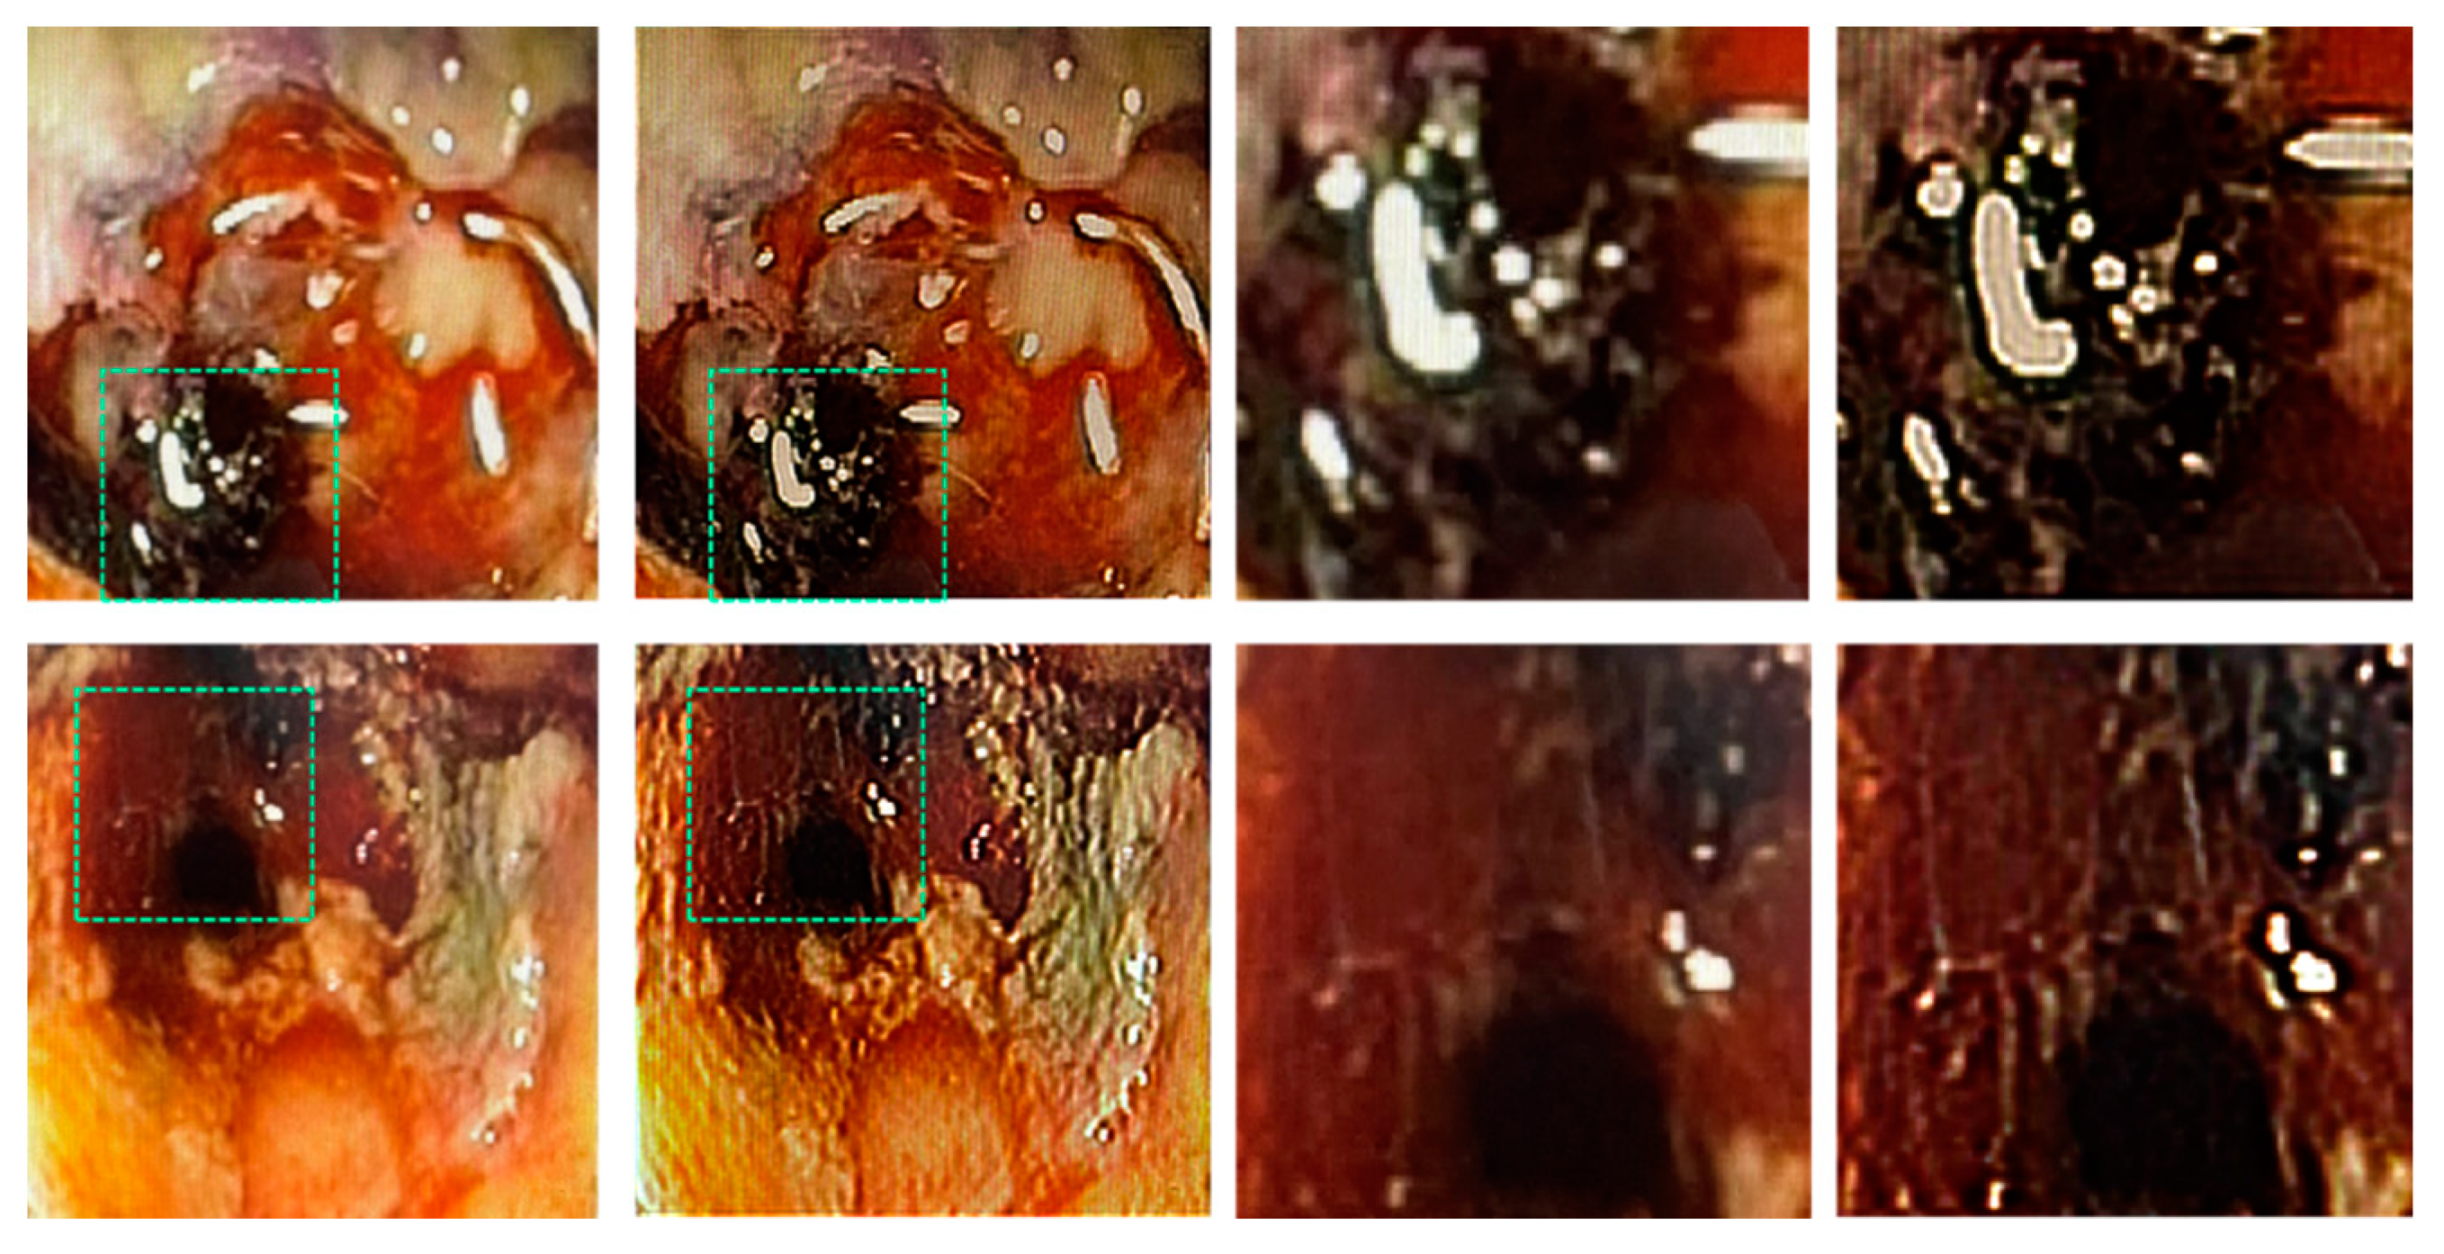

To demonstrate the application of LR2A to real applications in day-to-day life, medical images were obtained from surgeons. A 65-year-old patient, male with a known case of prostrate cancer had radiotherapy about a year ago. He developed bleeding and mucous discharge from the anus. The colonoscopy finding shows mucosal pallor, telangiectasias, edema spontaneous hemorrhage and friable mucosa. It can be noted that the mucosa was congested with ulceration stricture. The images were captured using colonoscope Olympus system and CaptureITPro medical imaging software. The direct images obtained using the colonoscope are shown in Figure 7(a) and 7(e). The IPSF can be synthesized in computer or an isolated dot can be taken from Figure 7(a), padded with zeros and used as the reconstructing function. In this study, the IPSF was synthetic [38,39]. The different color channels were extracted from the image and processed separately using synthetic IPSF and LR2A and then combined as discussed in [38]. The reconstructed images are shown in Figure 7(b) and 7(f). The magnified regions of Figure 7(a) and 7(b) are shown in Figure 7(c) and 7(d) respectively. The magnified regions of Figure 7(e) and 7(f) are shown in Figure 7(g) and 7(h) respectively. The red region indicates Telangiectasias and the black region shows necrosis which is the death of body tissue. The yellow region shows mucosal sloughing and the magnified region shows necrotic area with dead mucosa.

Figure 7. Experimental colonoscopy results. Red region – Telangiectasias; black region – necrosis which is the death of body tissue; yellow region – mucosal sloughing; magnified region – Necrotic area (dead mucosa).